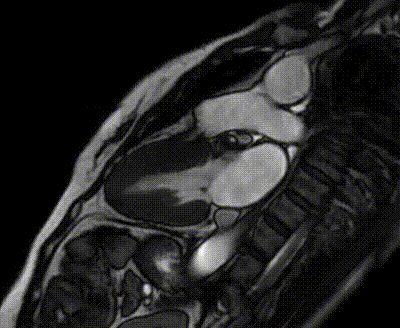

(两腔心电影序列)